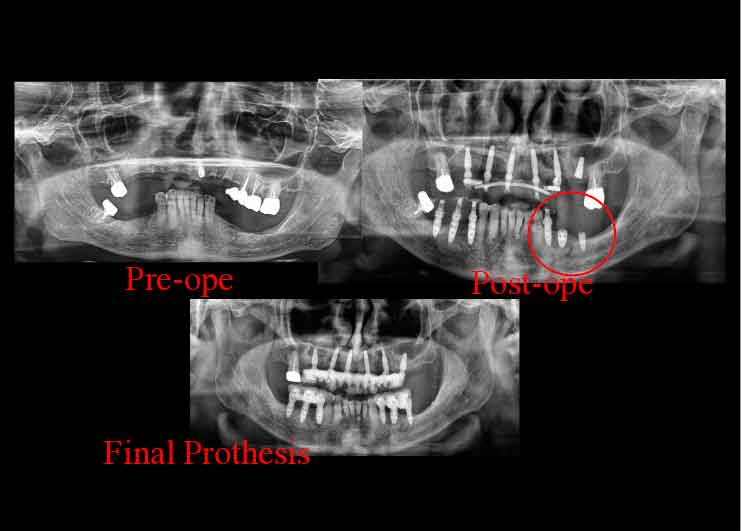

Case2. 68歳男性

下歯槽神経近くにインプラントを埋入したケース。

歯を失った下あごの骨が大きく吸収し、下歯槽神経の出入り口であるオトガイ孔が表面に近い部分に出てきています。そこで、X-ガイド使用により、下歯槽神経を避けた手術を行いました。

CTスキャンを撮影後、下歯槽神経の位置を明示した3D模型を作製。

DTX Studioで、下歯槽神経の位置とインプラントの埋入方向、深度を詳細に検討し、神経にダメージを与えないインプラントの位置をシミュレーション、X-ガイドによるナビゲーション手術を行いました。

DTX Studioで、下歯槽神経の位置とインプラントの埋入方向、深度を詳細に検討し、神経にダメージを与えないインプラントの位置をシミュレーション、X-ガイドによるナビゲーション手術を行いました。

インプラントでしっかり噛めるようになったことで筋肉がしっかりし、お肌にもハリが出て、若々しさを取り戻されました。

五十嵐歯科ではこのように、表情筋の回復まで考慮した治療を行います。